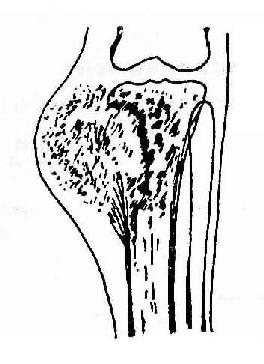

3.混合型骨肉瘤(Osteosarcomamixed type) 其X线表现为介于上述两型间,有不同程度的骨膜反应及骨质改变(图2-64)。

图2-64 胫骨上端骨肉瘤(混合型)显示软组织肿块内团状瘤骨,有三角型骨膜反应,胫骨上端有瘤骨增生及溶骨破坏。